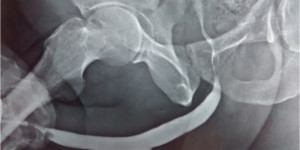

• X-ray studies, Ascending urethrogram.

• This test involves placing a fine catheter into the urethral opening and injecting contrast media .The narrowed segment and the length of narrowed segment can be visualized.